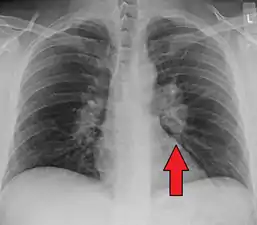

Hilar adenopathy especially on the person's left (AP CXR)

Hilar adenopathy especially on the person's left (lateral CXR)

Chest radiograph changes are divided into four stages:[105]

- bihilar lymphadenopathy

- bihilar lymphadenopathy and reticulonodular infiltrates

- bilateral pulmonary infiltrates

- fibrocystic sarcoidosis typically with upward hilar retraction, cystic and bullous changes

Although people with stage 1 radiographs tend to have the acute or subacute, reversible form of the disease, those with stages 2 and 3 often have the chronic, progressive disease; these patterns do not represent consecutive "stages" of sarcoidosis. Thus, except for epidemiologic purposes, this categorization is mostly of historic interest.[28]